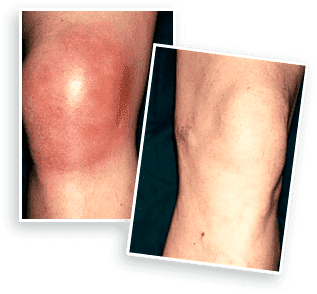

- Allevia anche i dolori articolari più forti. Restituisce la comodità del movimento. Ripristina la normale circolazione sanguigna, riduce il gonfiore.

- Allevia l’infiammazione, impedendo il danneggiamento dell’articolazione e prevenendo danni irreversibili. Avvia il processo di recupero delle articolazioni.